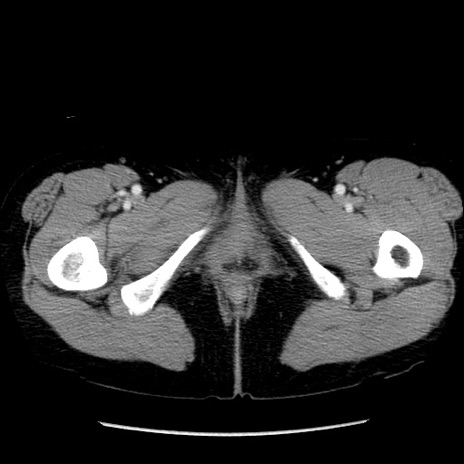

矢状断像

【症例】50歳代女性

【主訴】下腹部痛

【現病歴】本日朝より下痢2回あり。 昼食を食べた後、嘔吐3回、下腹部痛認め、症状軽快せず、当院救急搬送。

最終食事:本日昼(生ものなし)。 昨日の夜、刺身を食ぺたとのこと。周囲に同様の症状の者なし。普段、排便は毎日あるとのこと。

【既往歴】卵巣癌術後(8年前に当院で卵巣摘出)

【身体所見】 意識清明、腹部:平坦、腸蠕動音→、やや硬、下腹部自発痛・圧痛あり、反跳痛あり、筋性防御なし。

【データ】WBC 16000、CRP 0.01